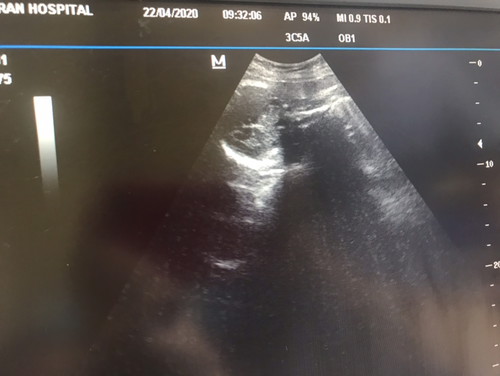

มีคันบอกว่าถ้าขึ้นตัวMเหมือนในภาพ จะเป็นผู้ชาย ถ้าขึ้นตัวFจะเป็นผู้หญิง จิงไหมคะ มีใครรุ้บ้างเอ่ย

น่าจะชายนะคั